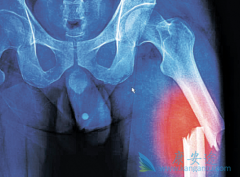

骨髓瘤患者的临床表现往往是身体多器官,多部位的,同时,由于人们对这个病认识不充足,导致对某些常见 骨髓瘤症状 表现,比如腰酸背痛,关节疼痛,感染现象等,常常出现误诊误治的现象,最终可能会延误治疗时机,影响预后。   如何识破那些引起骨髓瘤 ...